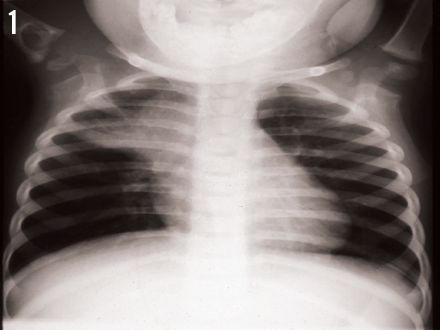

Radiographs of the right shoulder demonstrated a large cystic lesion in the proximal humerus with a lytic process extending across the physis into the epiphysis proximally. A large paratracheal lymph node also was noted on radiographs of both the chest (Figure 1) and the shoulder (Figure 2).

How do you interpret these images?